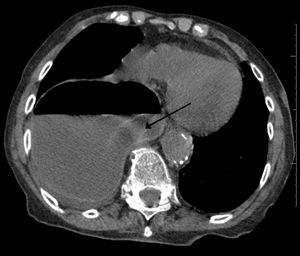

| This is a photo of a peritoneopericardial diaphragmatic hernia in a cat. The photo was taken during necropsy from the right side of the cat. To the left is the abdomen, where part of the liver and the gall bladder can be seen. The diaphragm is in the middle. To the right is the thorax. The largest object seen in the thorax is the rest of the liver. Just to the right of that is the heart. The liver was connected to itself through a small hole in the diaphragm (not seen). | |